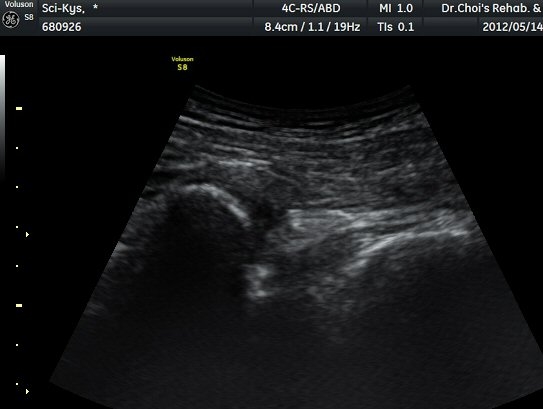

¾ûµ¢ÀÌ Á°ñ¿¡¼­ Á°ñ½Å°æ Ⱦ´Ü¸é°Ë»ç¿¡¼­ ´ëµÐ±Ù°ú quadratus femoris »çÀÌÀÇ ±Ù¸·

°æ°èºÎ¿¡¼­ Á°ñ½Å°æÀÌ °üÂûµÇ´Âµ¥ ³»Ãø Á°ñ°áÀý(ischial tuberosity) ÃøÀ¸·Î Ä¡¿ìÃÄ

ÀÖ´Â °ÍÀ¸·Î ÆÇ´ÜµÈ´Ù(±×¸² 1, 2, 3).